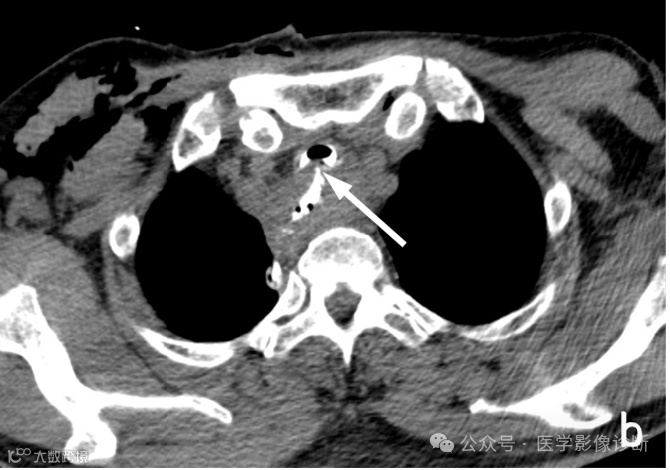

患者,男性,67岁,食管癌术后。

轴位 CT 显示食管癌术后变化(a, b)。然而,由于临床提供的申请表没有提醒,放射科医生只描述了术后变化,没有提及气管食管瘘。多平面成像(MPR)可以更好地显示瘘管。根据口服造影剂的使用情况,放射科医生应该明白医生想要观察是否发生了瘘管。